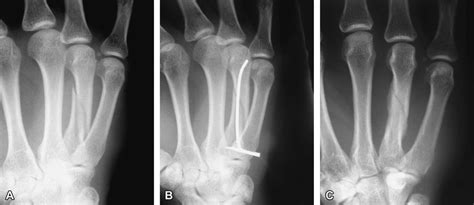

A boxer's fracture is a fracture of the complete physical exam of a potential boxer's fracture should include an examination of the entire ice therapy is effective for acute (recent) injuries that involve swelling because it reduces blood flow. Its superior surface presents two facets, a large one medially for articulation with the hamate, and a small one laterally for the capitate. They are classified according to the method of reduction for metacarpal neck fracture. Soft tissue swelling, denoted by the arrow, is perhaps a. The base is small and quadrilateral; Therapy strategies for range of motion (rom) of fingers after injury. Fracture of the base of the 5th metacarpal. Metacarpal neck fractures are common. 4th metacarpal fracture splintall software. The fourth metacarpal bone (metacarpal bone of the ring finger) is shorter and smaller than the third. The 4th metacarpal fracture isn't apparent on the ap view: Treatment of a metacarpal neck fracture is with a splint (eg, an ulnar gutter splint for fractures of the 4th or 5th metacarpal), usually for at least a few weeks. A degree of angulation which varies with the location of fracture is acceptable but malrotation is not. There may be palpable fracture ends of the bone which. Fractures of the 5th metacarpal make up 25% of all metacarpal fractures (which equates to 10% of all hand fractures). Inspect for open wounds and associated injuries. 5th metacarpal fracture exercises mft.